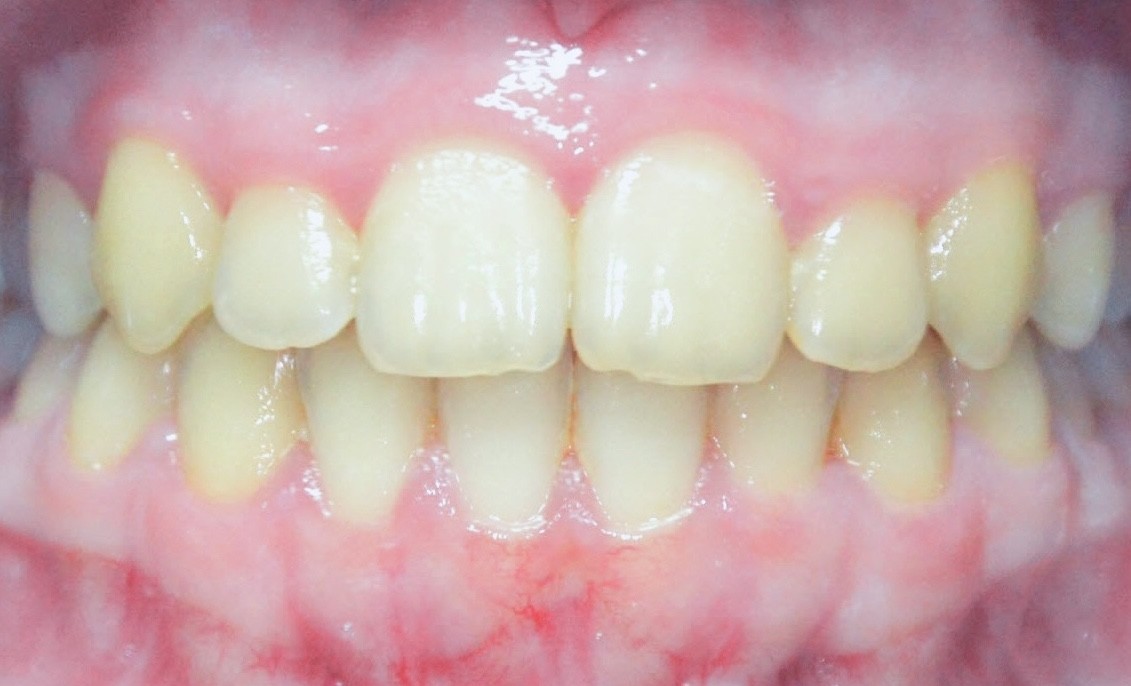

Jetzt stellen wir uns einmal vor, wir schauen in eine Mund und es sieht so aus wie auf Bild 2: Hier stimmt doch etwas nicht. Bei der genaueren Betrachtung fällt auf, dass der Oberkiefer auf der rechten Seite des Patienten zu schmal ist und nicht über den Unterkiefer beißen kann.

Dadurch stehen die unteren Zähne auf der Seite weiter außen als die oberen. Der Unterkiefer ist zu einer Seite verschoben. Diesen Biss nennen wir Kreuzbiss, da sich ab einem bestimmten Zahn – hier Eckzahn – die Seiten kreuzen. Zusätzlich ist die Mittellinie zur Seite des Kreuzbisses verschoben (grüne Striche).